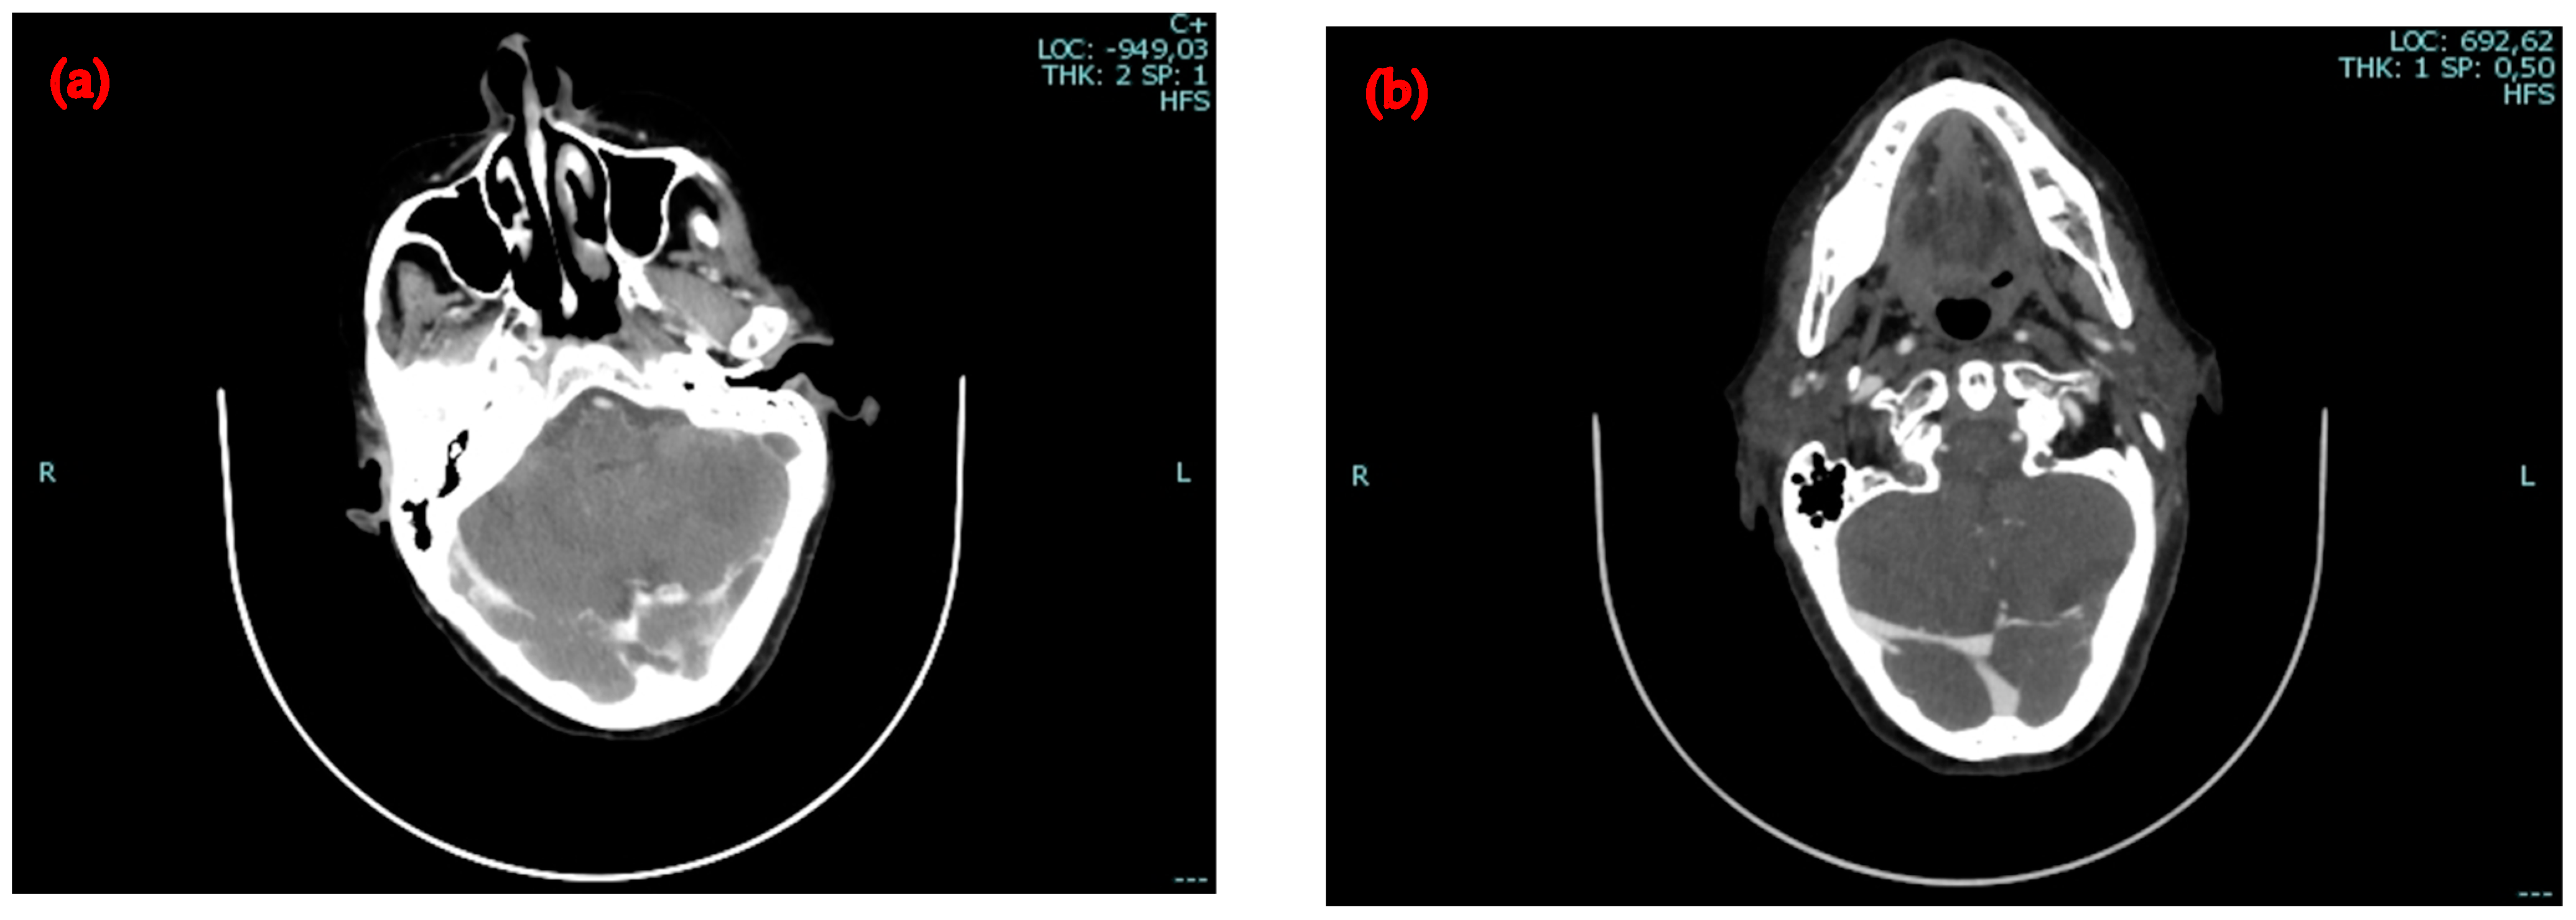

2.1. First Admission to the Hospital

2.2. Second Admission to the Same Hospital

2.3. Admission to the Infectious Diseases Unit of Our University Hospital